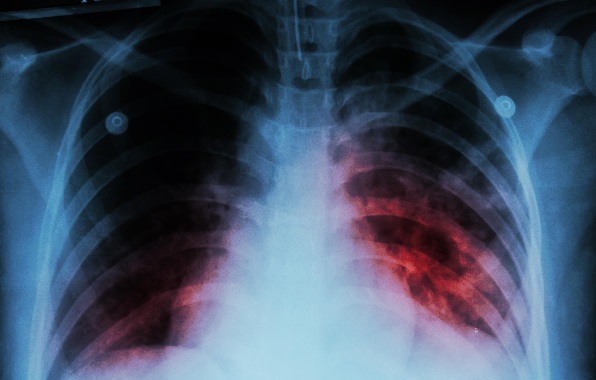

La tuberculosis es una enfermedad infecciosa causada por la bacteria Mycobacterium tuberculosis. Su principal impacto se da en los pulmones. Sin embargo, también puede comprometer órganos como los riñones, la columna vertebral y el cerebro.

Los síntomas pueden variar según la zona afectada. No obstante, existen signos frecuentes que permiten sospechar la enfermedad. Entre ellos, se encuentra la tos persistente, en ocasiones con presencia de sangre.

Además, se registran fiebre, escalofríos y sudores nocturnos. También pueden aparecer pérdida de peso sin causa aparente, fatiga y debilidad. La detección temprana resulta clave para iniciar el tratamiento.